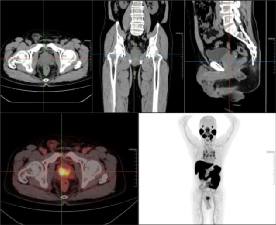

老年男性,前列腺增生病史,发现左侧颈部肿块多年,排尿困难,分叉5年,血精,怀疑前列腺肿瘤。PET/CT图如下。第一排为CT图,第二排分别为融合图、MIP图。

左侧颈部、颌下腺下后方、纵隔内(2R、4R、4L、5、6、7、8)及双侧肺门多发肿大淋巴结影,大者位于左侧颈部,最大截面约28.5mmX20.0mm,放射性摄取增高,SUVmax6.80,左侧颌下腺受压移位,考虑淋巴结转移灶,建议穿刺病理检查。

前列腺体积增大,并向前上凸入膀胱,腺体密度欠均匀,最大横径约55.3mm,前后径约42.5mm,腺体内点、条状高密度影,放射性摄取局限性增高,腺体中央部和外周部为著,摄取增高范围约38.1mmX27.3mm,SUVmax7.09,前列腺包膜局部略毛糙,考虑前列腺Ca,肿瘤突破包膜不除外。

经PSMA PET/CT显像检查准确发现了隐匿的转移灶,临床医生及时调整穿刺位点及治疗策略。